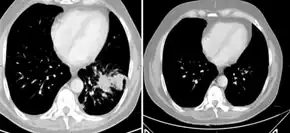

Abiraterone acetate, sold under the brand name Zytiga among others, is a medication used to treat prostate cancer.[1] Specifically it is used together with a corticosteroid for metastatic castration-resistant prostate cancer (mCRPC) and metastatic high-risk castration-sensitive prostate cancer (mCSPC).[3][4] It should either be used following removal of the testicles or along with a gonadotropin-releasing hormone (GnRH) analog.[3] It is taken by mouth.[1]

Prostate cancer

Abiraterone acetate is used in combination with prednisone, a corticosteroid, as a treatment for mCRPC (previously called hormone-resistant or hormone-refractory prostate cancer).[3][16][7][6] This is a form of prostate cancer that is not responding to first-line androgen deprivation therapy or treatment with androgen receptor antagonists. Abiraterone acetate has received Food and Drug Administration (FDA) (28 April 2011), European Medicines Agency (EMA) (23 September 2011), Medicines and Healthcare products Regulatory Agency (MHRA) (5 September 2011) and Therapeutic Goods Administration (TGA) (1 March 2012) approval for this indication.[3][16][7][6] In Australia it is covered by the Pharmaceutical Benefits Scheme when being used to treat castration-resistant prostate cancer and given in combination with prednisone/prednisolone (subject to the conditions that the patient is not currently receiving chemotherapy, is either resistant or intolerant of docetaxel, has a WHO performance status of <2, and his disease has not since become progressive since treatment with PBS-subsidised abiraterone acetate has commenced).[17]

In people previously treated with docetaxel survival is increased by 3.9 months (14.8 months versus 10.9 months for placebo).[19]

In people with castration-refractory prostate cancer but who had not received chemotherapy those who received abiraterone acetate had a progression-free survival of 16.5 months rather than 8.3 months with placebo. After a median follow-up period of 22.2 months, overall survival was better with abiraterone acetate.[20]